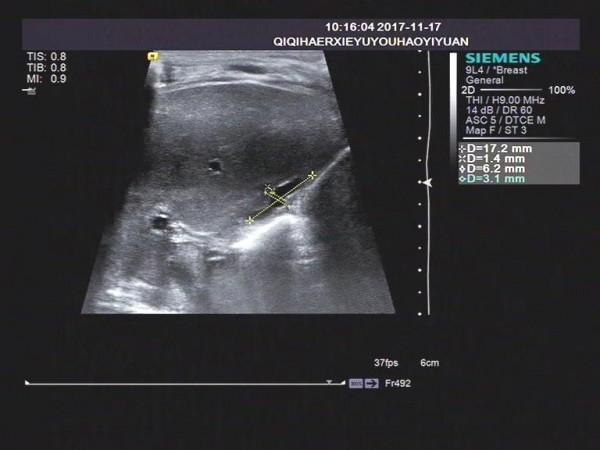

病例1

1)膽囊大小尚正常,但形態僵硬,邊緣不自然。長度可達到2cm左右,內徑大於0.4cm,可有小的憩室樣結構,部分形似臘腸。

2)小膽囊,長度小於1.0~1.5cm,內徑0.2cm,充盈差。

3)膽囊小而且無充盈,僅可見膽囊痕跡。

膽囊的聲像主要表現為:飢餓和餐後狀態下(建議進奶0.5小時,1小時多次觀察),膽囊形態均偏小或有假腔僅呈縫隙狀液性暗區。膽囊切面形態失常、不規則,壁毛糙,僵硬,部分病例可見雙邊回聲,進食後膽囊大小無變化。